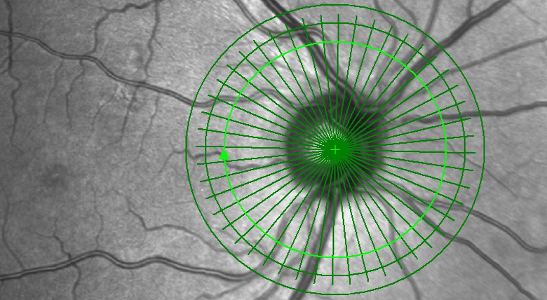

Glaukomscreening – Augendruckmessung, Tagesdruckprofil, Gesichtsfeldmessung, Pachymetrie (Messung der Hornhautdicke), hochauflösendes OCT der Papille in 3 verschiedenen Abständen vom Sehnerven. Das Glaukom (Grüner Star) ist eine meist schleichende Erkrankung, die meist wegen einer Augendruckerhöhung zu einem Schaden am Sehnerven und damit zu einer Gesichtsfeldeinschränkung führen kann. Nicht behandelt kann ein Glaukom zur Erblindung führen. Der Vergleich von Aufnahmen, die zu unterschiedlichen Zeitpunkten aufgenommen wurden, ermöglicht einen genauen Vergleich von Krankheitsverläufen.